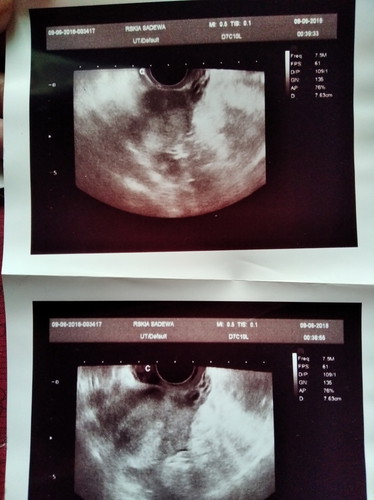

PCOS dan 2 garis merah

Pengen cerita sedikit tentang pengalaman saya. Saya penderita PCOS yg Alhamdulillah setelah penantian 2 th akhirnya Allah beri kami kado terindah tepat di ulang tahun pernikahan kami. Banyak yg tanya promil dmn Bun? Minum obat apa Bund? Dan msh banyak lg. Alhamdulillah tanpa promil kami diberi kepercayaan oleh Allah. Kuncinya menurut kami hanya percaya pd Allah pasti Allah akan berikan diwaktu yg tepat. Lbh mendekatkan diri pd Allah. Buat bunda yg mau bertanya tentang PCOS atau lainnya boleh dengan senang hati saya akan berbagi. SEMANGAT PEJUANG DUA GARIS MERAH ♥️